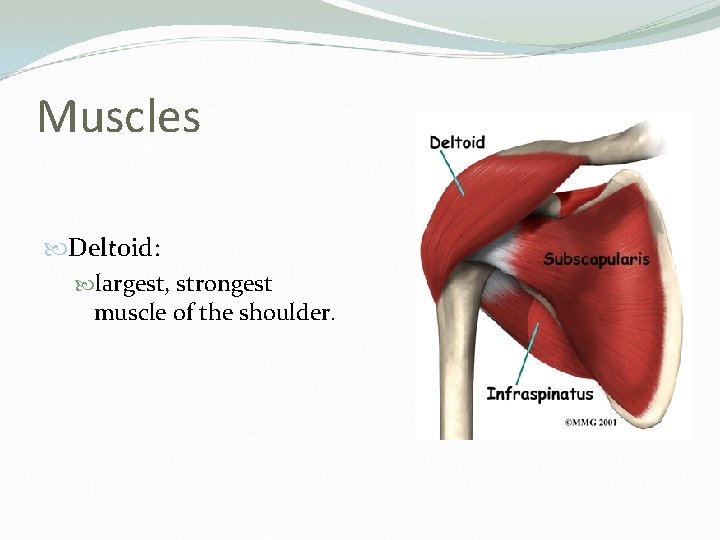

Muscles Deltoid: largest, strongest muscle of the shoulder.